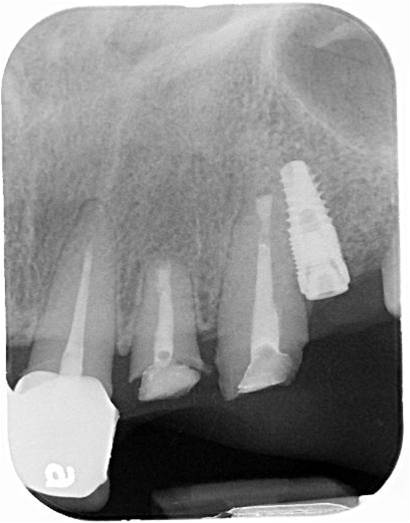

手術前電腦斷層評估